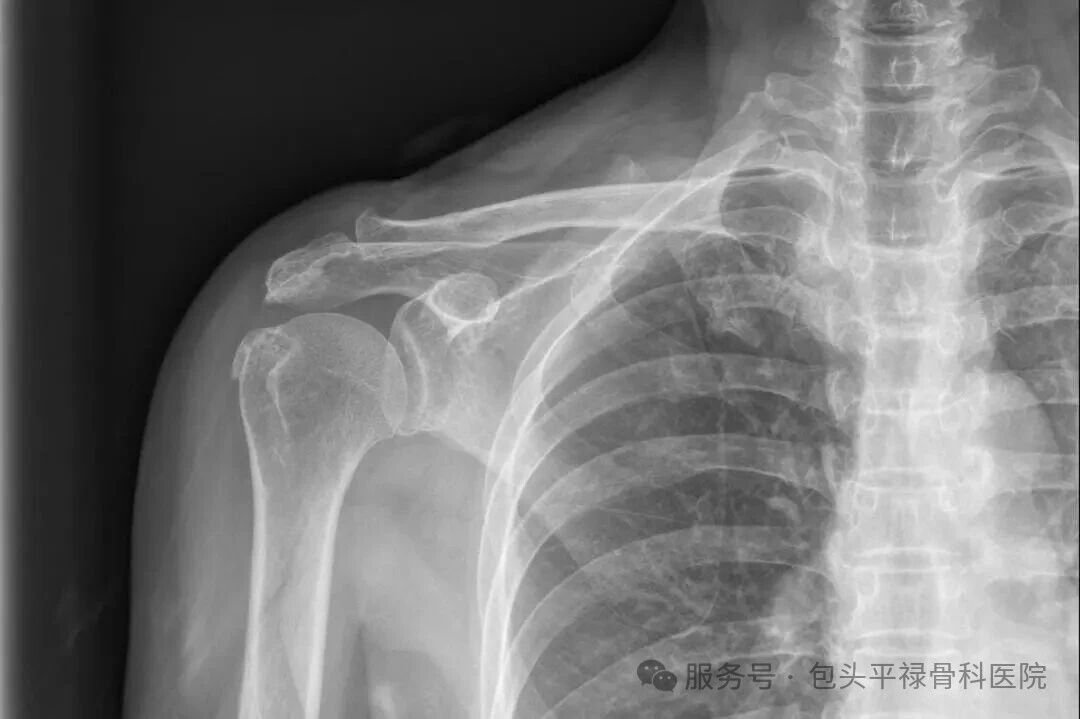

STOP!这个锅,“肩周炎”可不背!这种“抬臂痛”的背后,很可能藏着一个被你忽视的“元凶”——冈上肌损伤。

我们的肩膀之所以能360度灵活转动,靠的不是一根骨头,而是一个由四块肌肉组成的“团队”,它们像袖套一样包裹着肩关节,医学上称之为“肩袖”,而冈上肌,就是肩袖团队中最核心、最容易受伤的成员。

简单来说,冈上肌(Supraspinatus)是一块位于肩胛骨和上臂骨之间的肌肉,其核心作用是帮助抬臂并稳定肩关节,尤其在抬臂初期和肩关节外展时发挥关键作用。长期劳累、反复举臂、扭拉或年龄相关退变,都会让冈上肌变得脆弱或发炎,进而引发疼痛和功能下降。